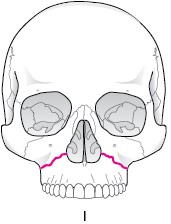

LefortT型骨折

梨状孔下部−犬歯窩−上顎洞壁−翼口蓋裂−翼状突起下部に達する骨折です。

鼻腔底より上方レベルでの水平骨折で、Lefortの3型の中では最も頻度は少ない骨折です。